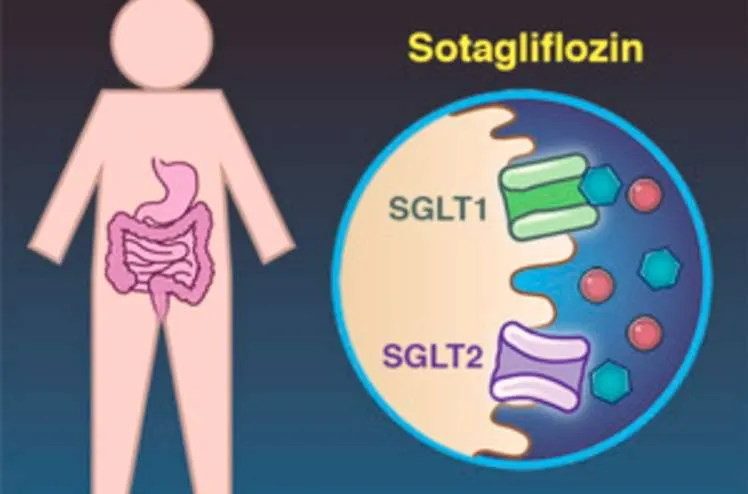

Uso do Sotagliflozina em Hipomagnesemia Refratária: Um Caso Clínico Relevante

Uso do Sotagliflozina em Hipomagnesemia Refratária: Um Caso Clínico RelevanteDescubra como o sotagliflozina pode mudar o manejo de um caso de hipomagnesemia severa e refratária. Saiba mais sobre este avanço terapêutico e seu impacto prático na nefrologia moderna!

Valkercyo Feitosa

2 anos atrás